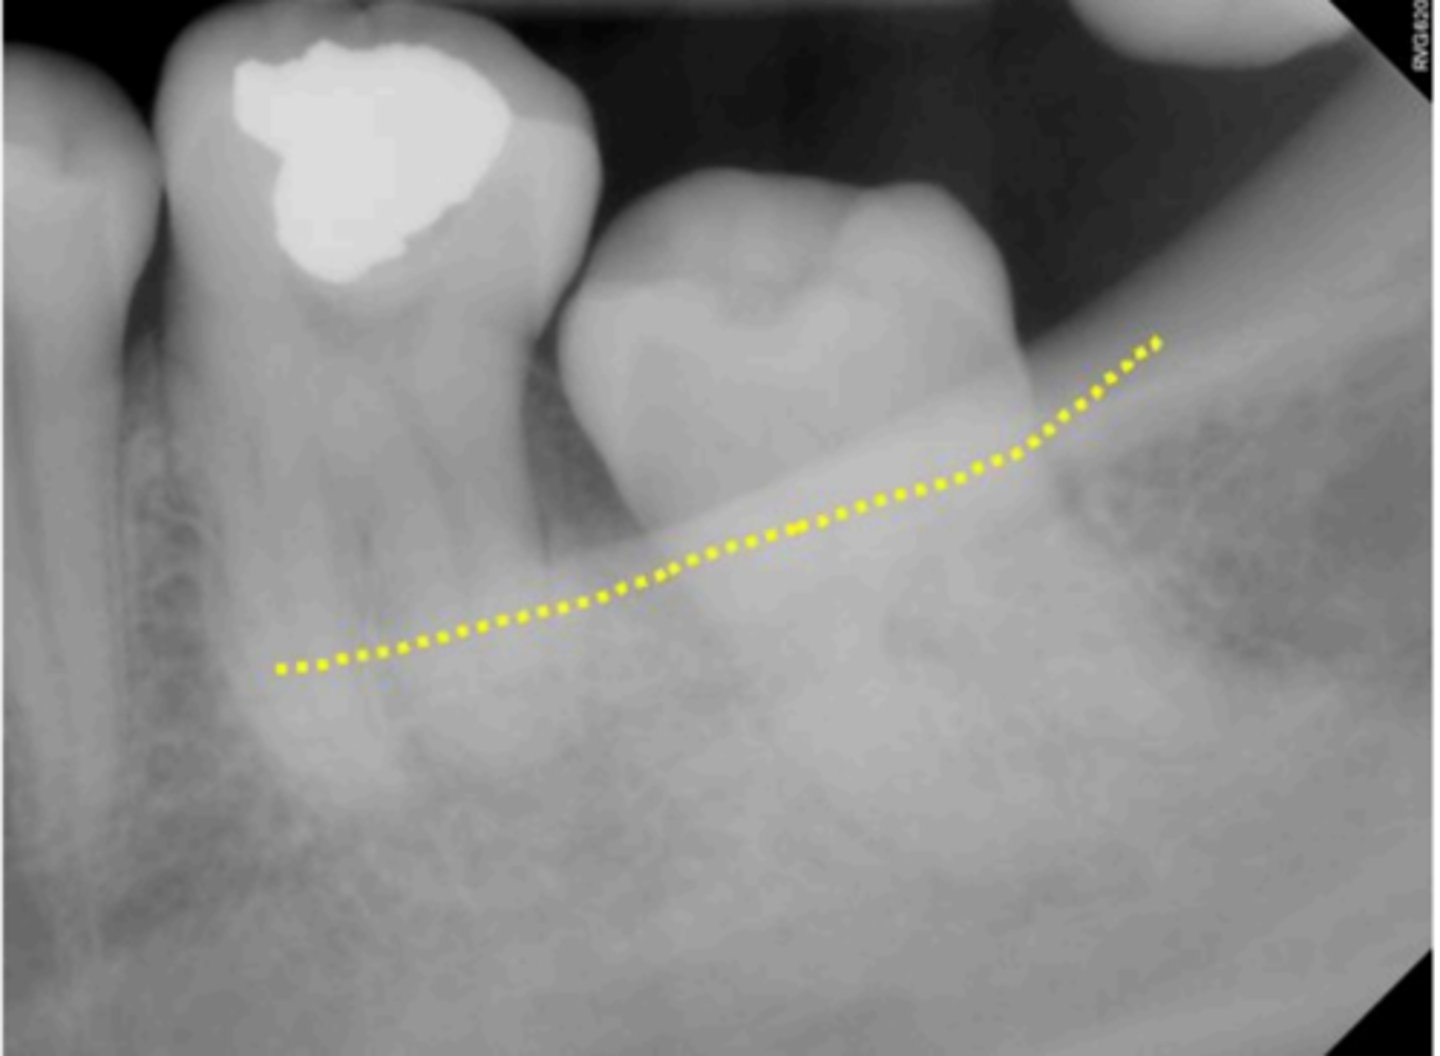

Mandibular canal

What is causing the thick radiolucent line surrounding the dotted line?

<p>What is causing the thick radiolucent line surrounding the dotted line?</p>

What is indicated by the dotted line?

<p>What is indicated by the dotted line?</p>